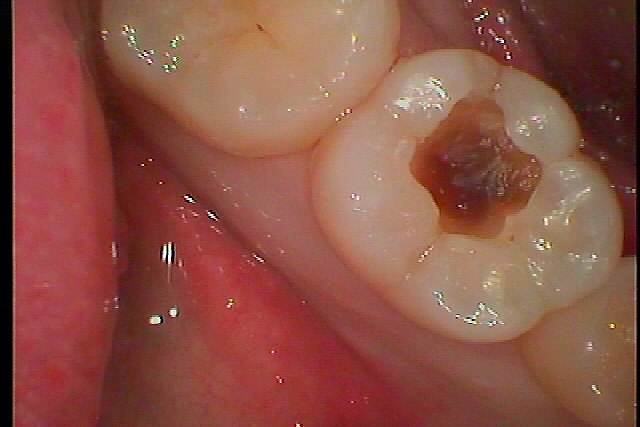

虫歯の治療です。 外見以上に虫歯が進行していることがあります。| |広島市安佐南区の歯科医院 虫歯の治療です。 外見以上に虫歯が進行していることがあります。 トップ お知らせ・ブログ 虫歯の治療です。 外見以上に虫歯が進行していることがあります。 虫歯の治療です。 外見以上に虫歯が進行していることがあります。 Web診療予約 初めての方へ 選ばれ続ける理由 院内設備について 歯が痛いしみる一般歯科 歯がぐらぐらする歯周病 健康な歯を保ちたい予防歯科 子供の虫歯予防をしたい小児歯科 銀歯をセラミックに審美歯科 白い歯を目指しませんか?ホワイトニング 矯正専門医がいるので安心矯正歯科 抜けた歯を補いたいインプラント・入れ歯 医院案内 スタッフ紹介 メリィハウス歯科クリニックオフィシャルホームページ ラベンダー歯科クリニックオフィシャルホームページ お知らせ・ブログ ホーム 診療科目 一般歯科 歯周病治療 予防治療 小児歯科 審美治療 ホワイトニング 矯正歯科 入れ歯・インプラント マウスピース矯正 初めての方へ 院長・スタッフ 設備紹介 医院案内・アクセス メニューを閉じる